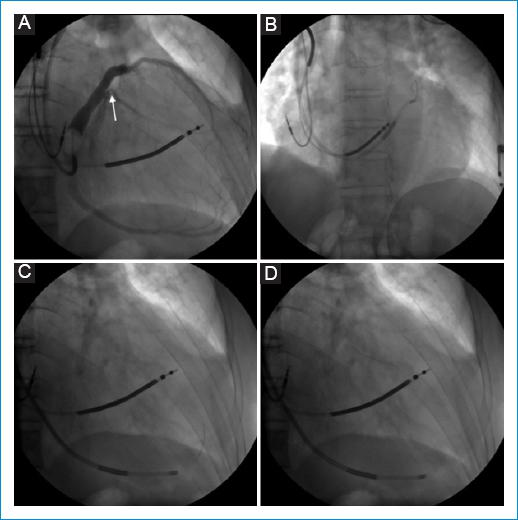

Figura 2 Abordaje inicial A: estenosis proximal de la vena posterolateral (flecha). B: Imposibilidad para canular por vía anterógrada la vena posterolateral. C: Primera camisa en la vena cardiaca media con el avance de la guía metálica a la vena posterolateral por vía retrógrada. D: canulación retrógrada de la vena posterolateral.

Se trata de un hombre de 67 años, con miocardiopatía chagásica, usuario de cardiodesfibrilador bicameral desde el año 2015 como prevención secundaria de muerte súbita, con fracción de eyección del ventrículo izquierdo (FEVI) del 25%, clase funcional III/IV de la New York Heart Association (NYHA) y estimulación ventricular derecha mayor del 40% debido a bloqueo auriculoventricular avanzado intermitente producto del progreso de su enfermedad, quien venía presentando síntomas de falla cardiaca descompensada con QRS basal de 200 ms (Fig. 1A). Se decidió llevar a terapia de resincronización cardiaca, por lo que se indicó explante del cardiodesfibrilador e implante de un resincronizador cardiaco. Bajo efectos de anestesia general, se hizo un abordaje percutáneo de la vena axilar izquierda con una punción directa guiada por ecografía. Se dejó retenida una guía metálica de soporte medio ATW 0.014 300 floppy (Cardinal Health Colombia SAS) a la altura de la vena cava inferior, sobre la cual se avanzó una camisa ATTAIN Select (6248VI-130 Medtronic) con la que se canuló el seno coronario en primera instancia. A través de esta camisa, se pasó un catéter balón ATTAIN Clarity (6225-Medtronic), con el que se logró una oclusión proximal del seno coronario para la realización de una venografía mediante la inyección de 10 ml de solución radioopaca que permitió identificar vasos venosos coronarios pequeños, específicamente una vena posterolateral un poco tortuosa y con estenosis proximal (Fig. 2A), que representó un obstáculo para su acceso anterógrado (Fig. 2B). En vista de lo anterior, se consideró la posibilidad de realizar un acceso retrógrado a dicho vaso, por lo que se canuló la vena cardiaca media y se dejó alojada en dicho vaso la camisa no deflectable ATTAIN Select. Se avanzó la guía metálica de soporte medio ATW 0.014 300 floppy hasta la porción proximal de la vena posterolateral y se logró flanquear la estenosis proximal (Figs. 2 C-D). Finalmente, el extremo floppy de la guía se alojó en el seno coronario. Se realizó una segunda punción de la vena axilar izquierda guiada por ecografía. Se pasó una segunda guía metálica de soporte medio ATW 0.014 300 floppy a la vena cava inferior, sobre la cual se avanzó una segunda camisa no deflectable CPS universal OC-W de 47 cm (PS2C021-St Jude Medical), con la que se canuló nuevamente el seno coronario. Se retiró la guía metálica de la camisa y se avanzó un catéter multi-snare 6 Fr × 10 mm × 125 cm (EN 20060-World Medical), con el cual se capturó y se exteriorizó la punta floppy de la guía (Figs. 3 A-B). Con ambos extremos de la guía metálica exteriorizados, y dada la dificultad del acceso a través de la estenosis proximal de la vena posterolateral y su riesgo de ruptura por tratarse de un vaso tortuoso y pequeño, se decidió introducir el electrodo soportado desde el extremo rígido de la guía, y de esta manera se avanzó el electrodo hasta la vena cardiaca media y luego de forma retrógrada a la vena posterolateral hasta su estenosis (Figs. 3 C-D), obteniendo así una adecuada captura biventricular sin estimulación diafragmática. El QRS estimulado fue de 150 ms (Fig. 1B).